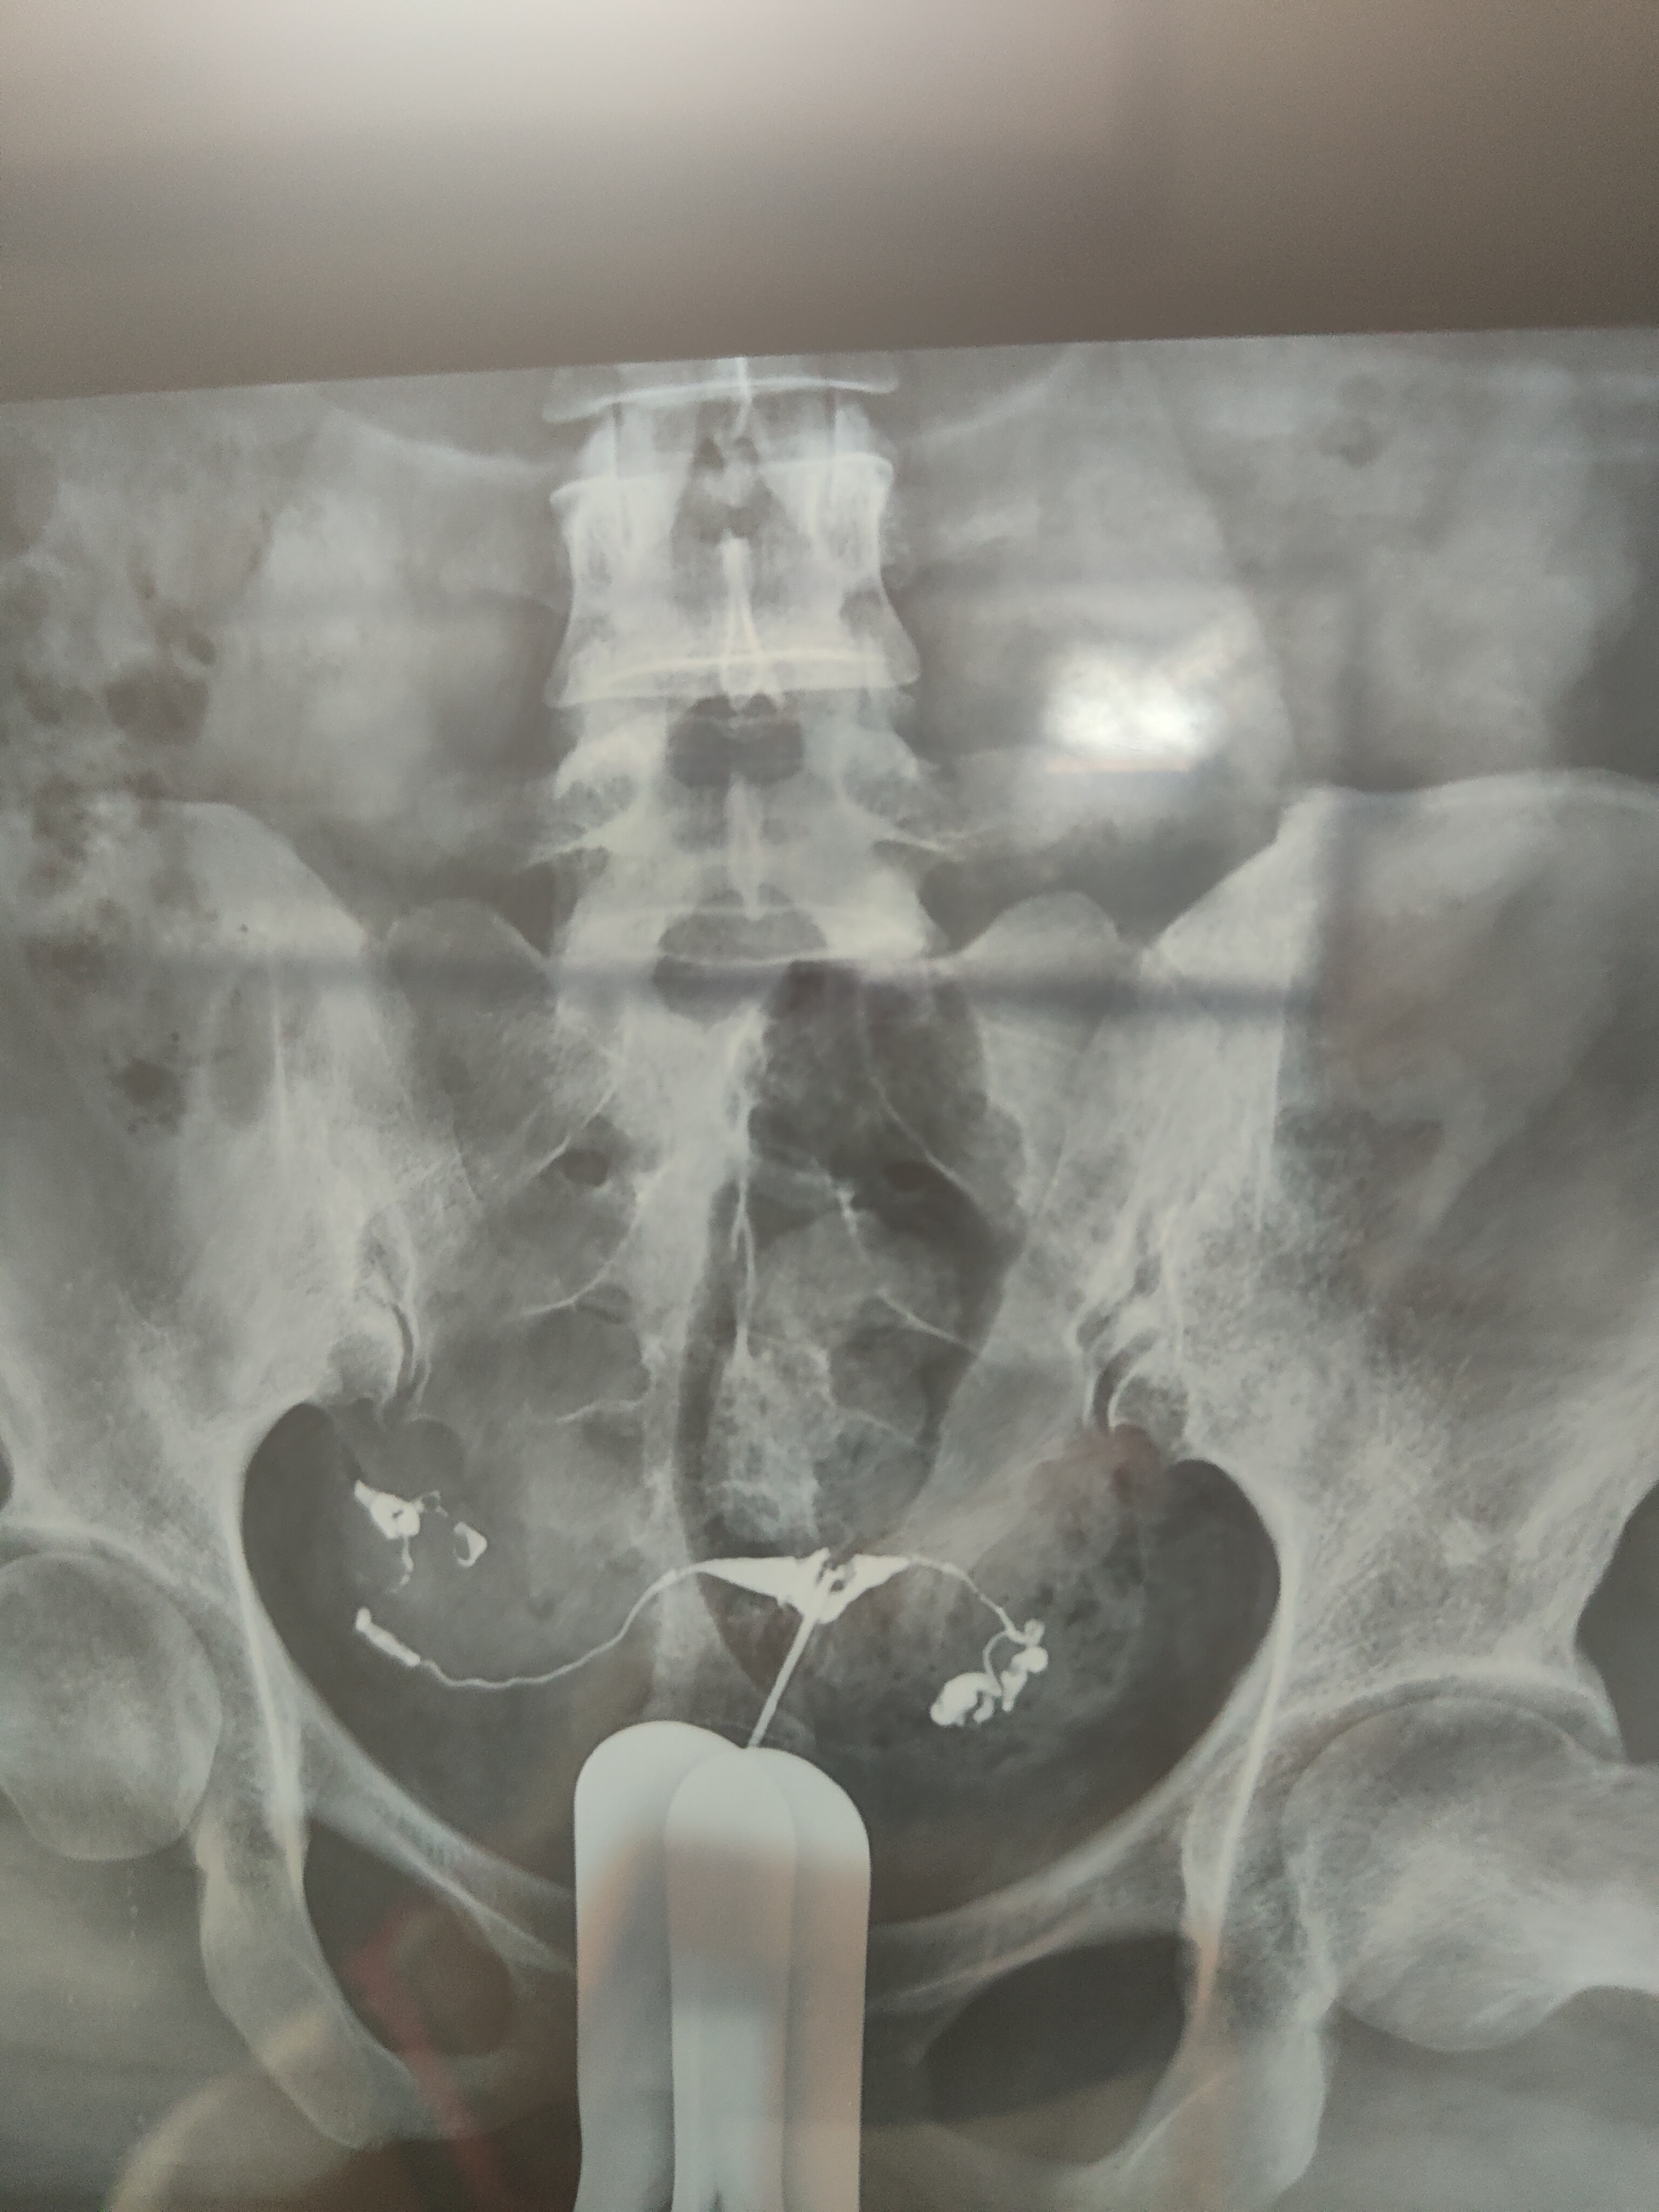

各位医生好,,前天做了输卵管造影,请帮忙看看这些造影片是正常的么?

双侧输卵管通畅,弥散好,正常造影,可以试孕。

你好,结果正常,放心吧,祝好孕。